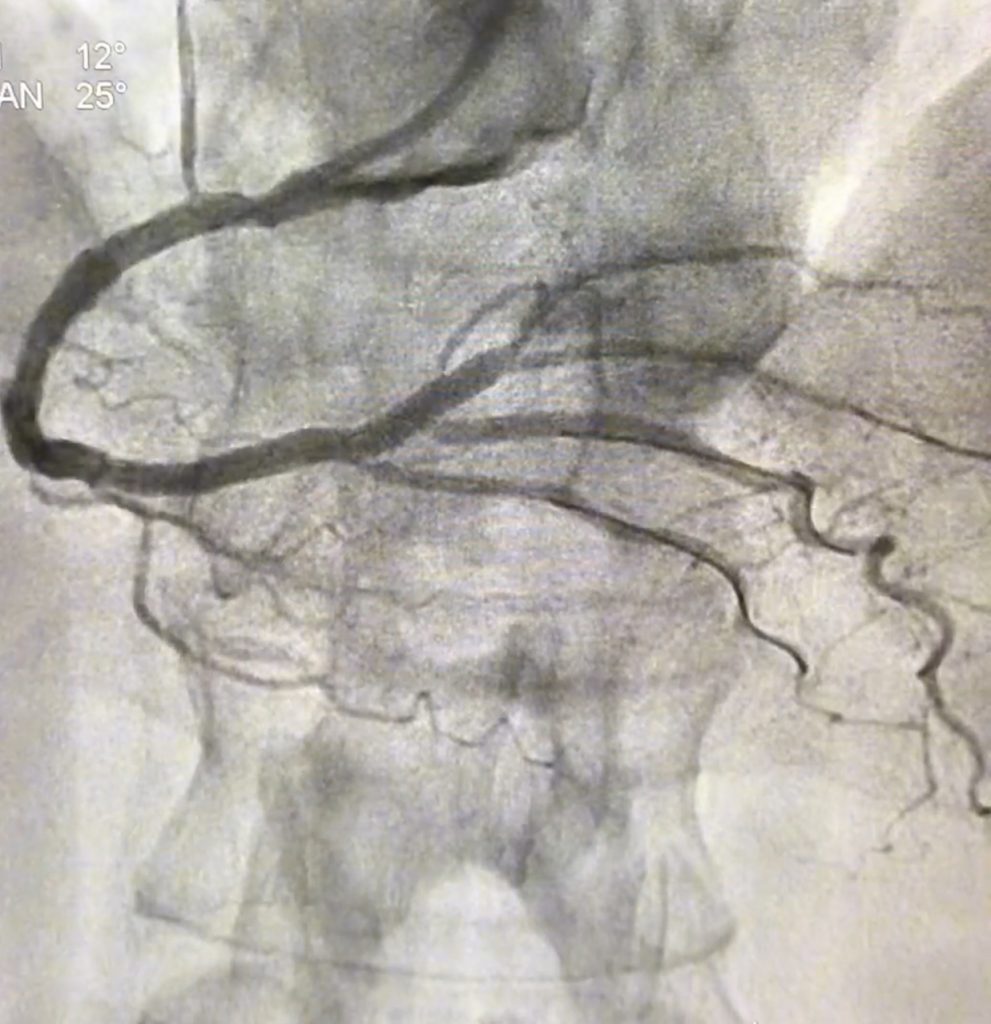

La coronariografía permite visualizar las arterias coronarias con contraste, identificando con precisión las obstrucciones responsables del infarto.